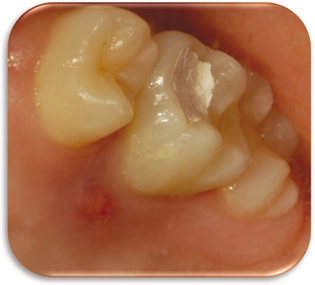

Figure 2

Pre-operative periapical x-ray.

Figure 2 Pre-operative periapical x-ray.